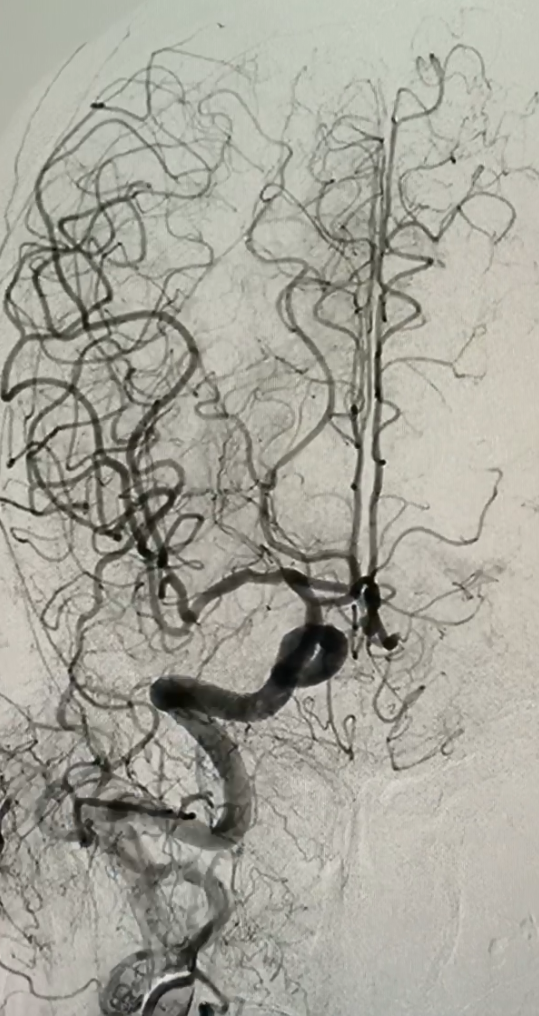

Cụ bà Đặng Thị Thể, 96 tuổi ở phường 1, thành phố Đông Hà đột ngột bị suy giảm tri giác, liệt nửa người bên phải được đưa vào Bệnh viện Đa khoa tỉnh Quảng Trị sau 1,5 giờ xuất hiện triệu chứng. Xác định người bệnh bị nhồi máu não cấp do tắc mạch máu, các bác sỹ khoa Hồi sức tích cực-chống độc và Đơn vị Đột quỵ của Bệnh viện phối hợp khoa Chẩn đoán hình ảnh tiến hành chụp cắt lớp vi tính sọ não không tiêm thuốc và chụp cắt lớp vi tính mạch máu não đồng thời mời bác sỹ khoa Nội tim mạch-lão học điều trị bằng thuốc tiêu sợi huyết đường tĩnh mạch. Hình ảnh chụp cắt lớp vi tính cho thấy người bệnh bị tắc hoàn toàn động mạch cảnh chung trái từ gốc, các bác sỹ Đơn vị Đột quỵ và Đơn nguyên Tim mạch can thiệp quyết định lấy huyết khối động mạch não dưới máy chụp X-quang số hóa xóa nền. Sau 1 giờ can thiệp, ê-kip của thạc sĩ-bác sỹ Phùng Hưng đã lấy rất nhiều cục huyết khối động mạch não, đưa dòng chảy của mạch máu vùng cổ và não bên trái thông trở lại, người bệnh được cải thiện tri giác và qua cơn nguy kịch. 24 giờ sau, hình ảnh chụp cắt lớp vi tính cho thấy tổn thương não không đáng kể.

Động mạch cảnh chung trái bị tắc (hướng mũi tên xanh)

Với sự hỗ trợ của máy chụp X-quang số hóa xóa nền, thạc sĩ-bác sỹ Phùng Hưng và các cộng sự đã mở đường vào lòng mạch máu của người bệnh, đặt sheat 5F vào động mạch đùi phải theo phương pháp Seldinger, luồn verteral catheter 5F + radifocus guidewire 0.035” vào động mạch cảnh chung trái rồi đặt neuron max 088 đến gốc động mạch cảnh chung trái, đưa sofia plus đến đoạn động mạch cảnh chung bị tắc để hút huyết khối, đặt PX-SLIM và wire sion 0.014 lên động mạch cảnh trong trái nội sọ kéo ra nhiều huyết khối đen. Sau can thiệp, động mạch cảnh trong não giữa trái của người bệnh thông hoàn toàn, tưới máu nội sọ trái TICI 2b, động mạch cảnh trong phải ưu thế, bàng hệ não trước trái. Đến ngày thứ 3 sau phẫu thuật, cụ bà Đặng Thị Thể đã hồi phục phần lớn các chức năng vận động, có sự nhận biết khi được gọi hỏi, cử động được và có cảm giác ở tay chân bên trái.